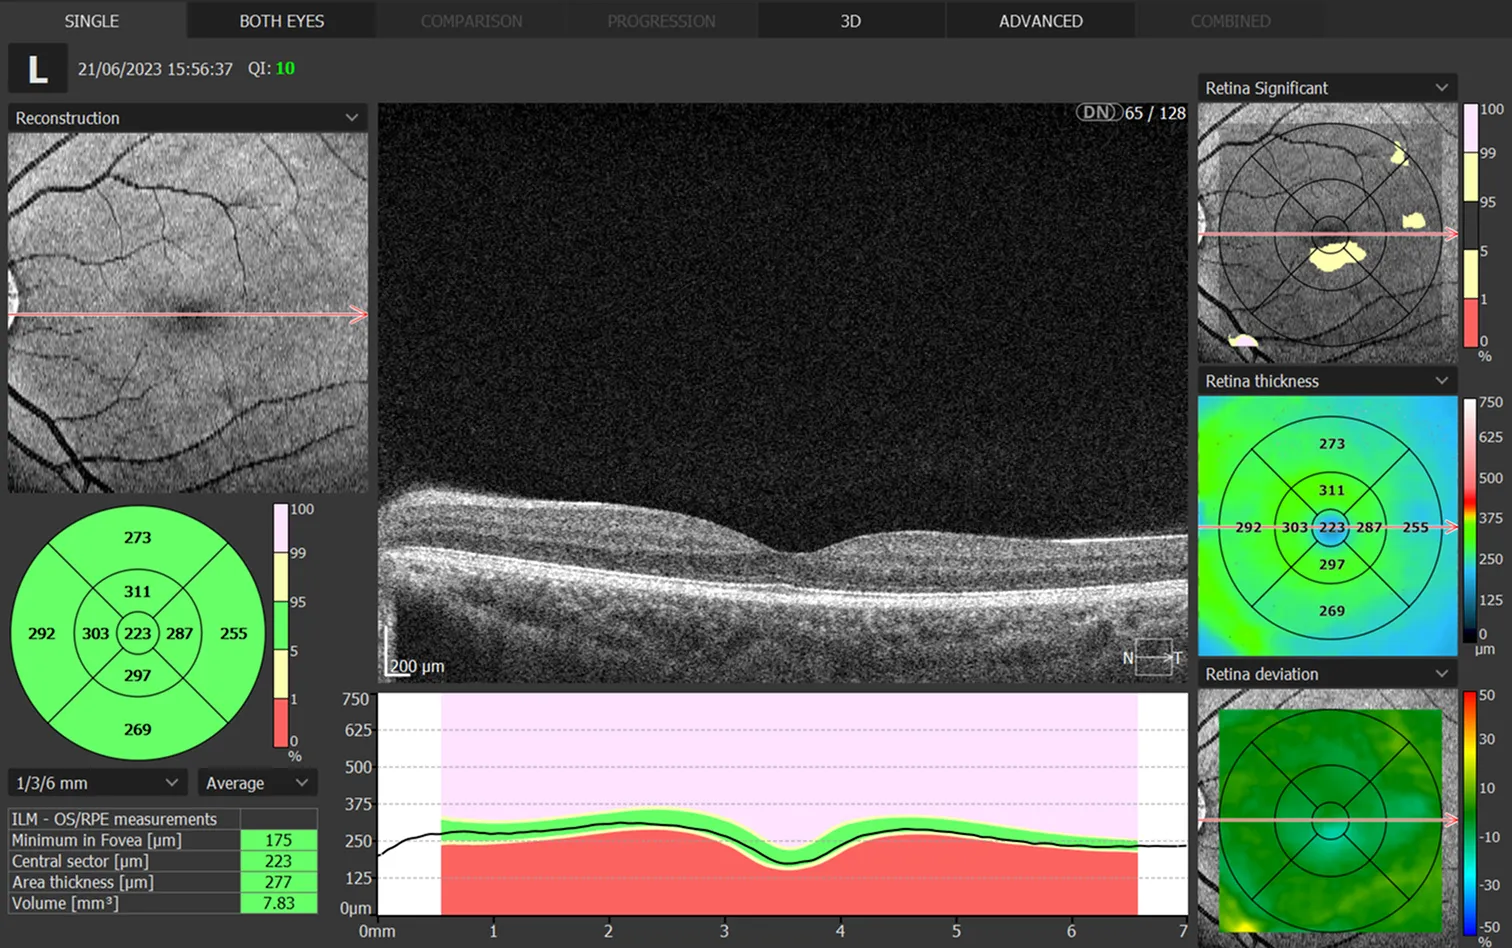

OCT provides detailed retinal imaging, using light to safely examine the interior structure of the eye. This allows optometrists to catch serious conditions in their earliest stages.